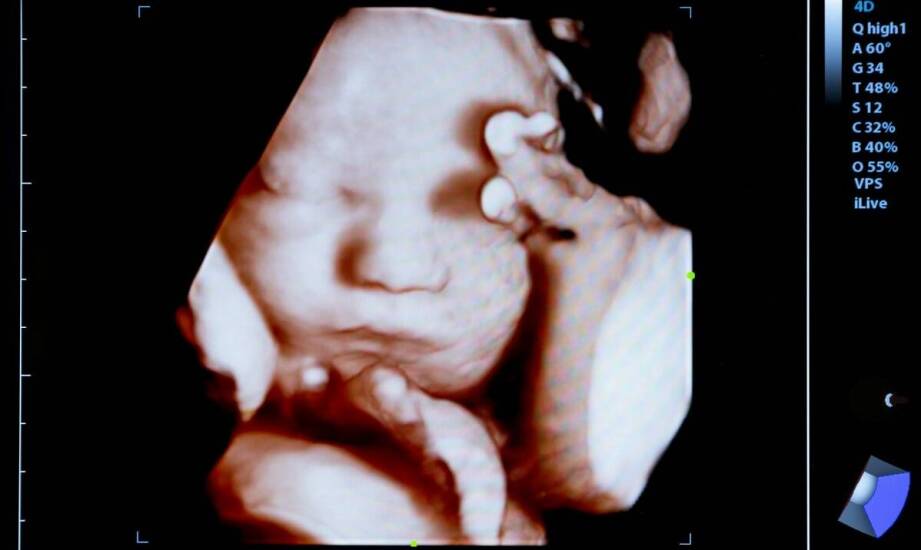

USG główki noworodka (USG przezciemiączkowe) pozwala szybko ocenić struktury mózgowia u niemowląt bez promieniowania i bez bólu. Badanie trwa zwykle 15–20 minut, nie wymaga specjalnego przygotowania i może być powtarzane. Największą wartością jest wczesne wykrycie nieprawidłowości, takich jak krwawienia śródczaszkowe czy wodogłowie, co ułatwia zaplanowanie dalszej diagnostyki i opieki.

USG przezciemiączkowe to badanie ultrasonograficzne wykonywane przez ciemiączko – naturalną, elastyczną przestrzeń między kośćmi czaszki dziecka. Przez to „okno akustyczne” fale ultradźwiękowe docierają do mózgowia i tworzą obraz na monitorze.

Przebieg jest prosty: na skórę głowy nakłada się żel, następnie osoba wykonująca badanie przykłada głowicę ultrasonografu i ocenia struktury mózgu w różnych przekrojach. W trakcie można poprosić rodzica o podtrzymanie spokojnej pozycji główki. Całość trwa około 15–20 minut.

Badanie jest nieinwazyjne, bezbolesne i nie emituje promieniowania. Dzięki temu można je powtarzać, aby obserwować rozwój dziecka lub monitorować zmiany w czasie.